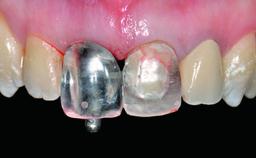

A 36-year-old male patient with a compromised maxillary central incisor was referred by his general dentist for consultation. The patient’s chief complaints were the gradual debonding of a temporary crown on the right central incisor and unsatisfactory esthetics due to an increasing diastema between the right central and lateral incisors. The patient reported a traumatic event some years previously, when a crown had been placed after root-canal treatment. The referring dentist wanted to provide a new crown restoration, but was concerned about the condition of the residual root. Anamnesis was negative for any other dental or periodontal pathology in the remaining dentition. The patient reported taking no medications: He was a smoker (10 to 15 cigs/day) and had realistic esthetic expectations.

Prosthesis Type FDP

Retention Screw-retained Screw-retained

Provisional Implant-Supported Prosthesis Prosthodontic margin > 3 mm apical to mucosal margin Prosthodontic margin > 3 mm apical to mucosal margin